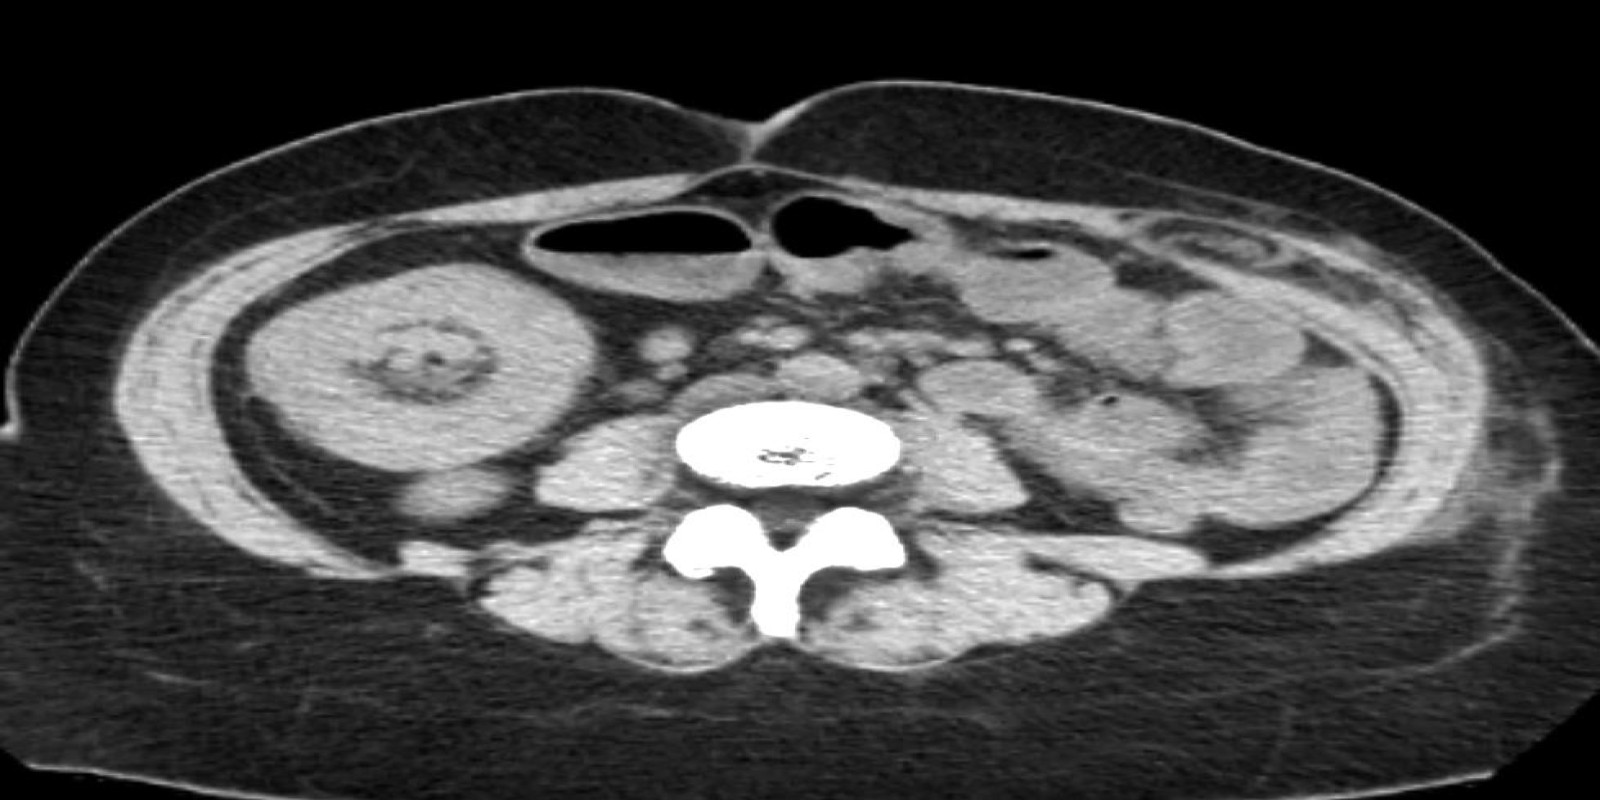

Caso Código 267B de Intussuscepção

Cod.: 267B